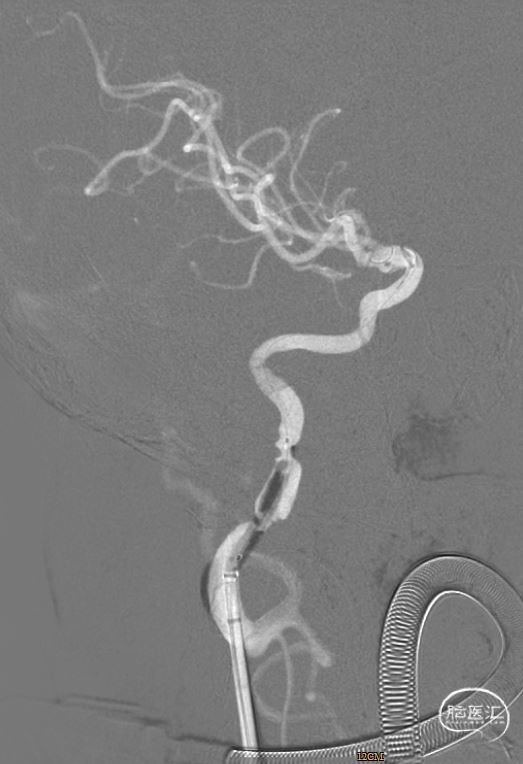

右股动脉处置入8F 股动脉鞘,分别沿鞘送入泥鳅导丝、5FH1动脉造影导管造影提示右侧颈内动脉C1段闭塞,考虑右侧颈内动脉夹层。

路径图下沿导引导管送入6F 颅内支持导管(6F*125cm)+微导管+微导丝(0.014*200cm)组合,在路径图引导下,将支持导管先端置于右侧颈内动脉C1段,造影显示前交通动脉有代偿。

路径图下将微导丝的先端小心通过右侧颈内动脉C1段闭塞段置于C5段,跟进微导管顺利通过颈内动脉闭塞段。

撤出微导丝,微导管造影确认在真腔内。

沿微导管送入取栓支架(6mm*30mm),准确对位后成功释放,撤出微导管,造影提示右侧颈内动脉及右侧大脑中动脉有前向血流,等待5分钟后,跟进颅内支持导管至颈内动脉C2段,缓慢回撤取栓支架,并沿中间导管抽吸,可见支架缠绕少量血栓,送入Synchro-2 微导丝3m至C7段,回撤中间导管,再次造影提示右侧颈内动脉C1段重度狭窄伴夹层样改变,观察10分钟血流较前减慢。